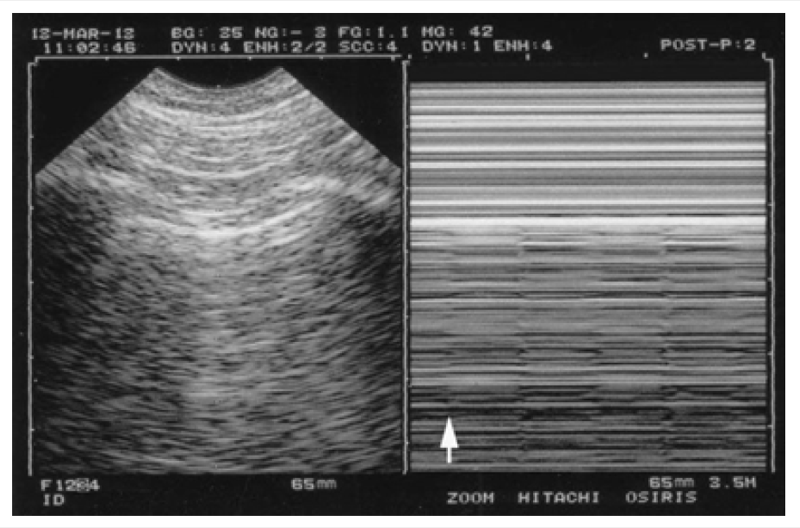

Correctly designed machines locate the real-time and M-mode images exactly side by side. Not “side by side.” Exactly side by side. Now an issue has to be known. Most laptop machines, from cheap to costly, display the M-mode with a lag when compared to the real-time image. This will prevent to locate immediately the pleural line with confidence in acute situations, when stress does not help.

We see two options. In one, the real-time image comes upstairs, small, with a large M-mode image downstairs; one must extrapolate, with haste, where the real pleural line is (Fig. 4).

In another, both images are displayed apparently side by side, but not exactly side by side (Fig. 5).

Fig. 5 M-mode and a wrong note. The arrows indicate the misconception. In very widespread machines, for unknown reasons, real time and M-mode are not exactly side by side. By bad providence, the lag corresponds to the intercostal muscle. In dyspneic patients, “sand” can be displayed from this level, i.e., above the pleural line. This will make more complex a diagnosis (pneumothorax) which asks to be, and is, simple – yet lung ultrasound does not need superimposed complexity. At the bottom is a musical score. The left note is ill defined, and the composer’s intentions are unclear. The notes at the right are perfectly defined; anyone can play them.

The perfect configuration we had in our 1982 ADR-4000 and our 1992 Hitachi 405, which both display both images exactly side by side, with no space for confusion, was not used again by the modern manufacturers, who, for incomprehensible reasons, display a gap, a lag. And nothing to rectify it. This lag corresponds roughly, bad luck, to the thickness of the intercostal muscle or more. The operator must guess the pleural line location with extreme haste (when there is no time for guesses) or, worse, risks to believe that the right image corresponds to the left one. Therefore, the unexperienced operator will think that the M-mode pleural line is this line at the level of the real-time pleural line; confusing the pleura with an aponeurosis will confuse the sand arising above the pleural line with a lung sliding, conclude “lung sliding present,” and miss the pneumothorax.

This configuration where both images are roughly but not exactly side by side is the worst. These concepts are not suitable for optimal lung ultrasound. They have been built by manufacturers unaware of the existence of lung ultrasound. This adds complexity in a field which is simple but not that simple, so let’s not add more.